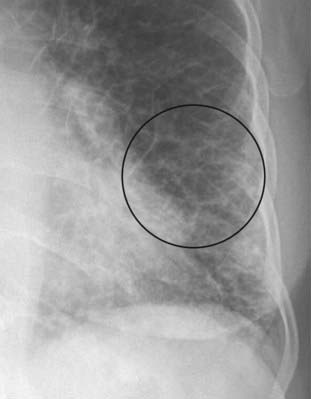

image

Figure 9-11 Kerley A lines.

The A lines (circle) appear when connective tissue near the bronchoarterial bundle distends with fluid. They extend from the hila for several centimeters in the midlung and do not reach the periphery of the lung like Kerley B lines do. A network of Kerley lines is produced in the lungs in patients with congestive heart failure producing the “prominence of the pulmonary interstitial markings” seen in that disease.